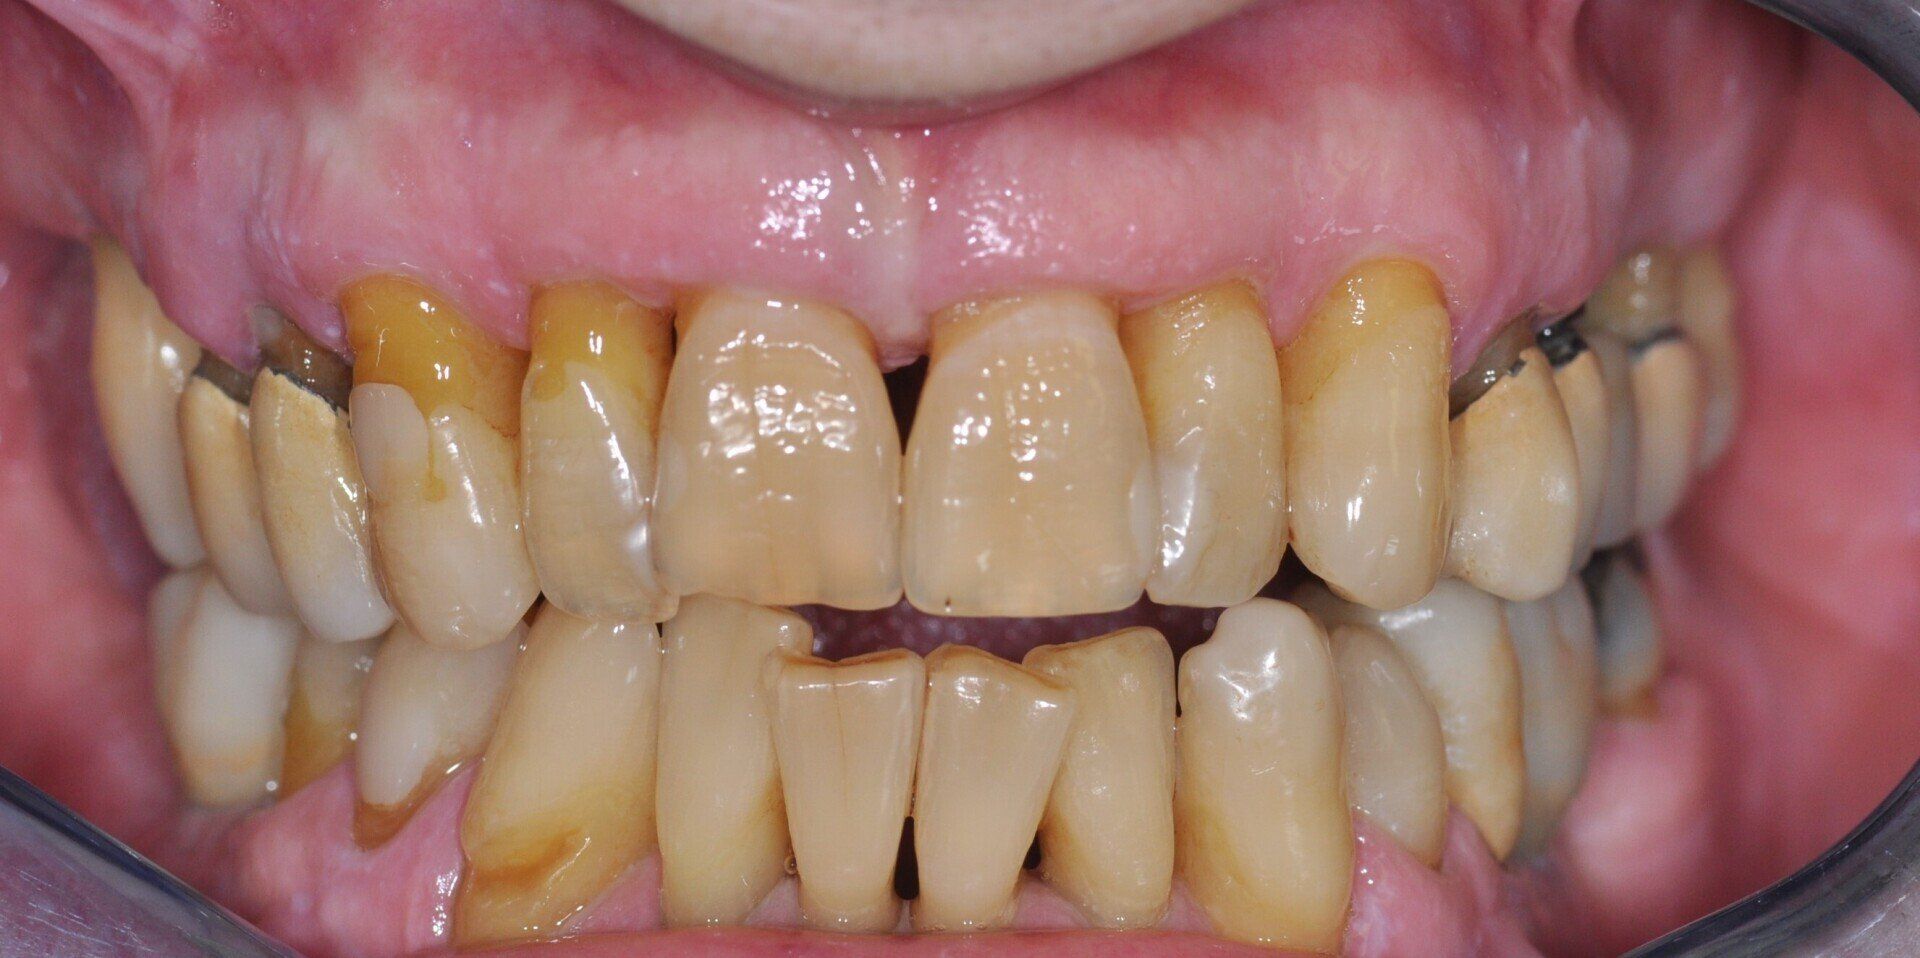

Fig. 1_Foto pre-operatoria di uno dei pazienti inclusi al tempo della chirurgia.

I pazienti considerati eleggibili all’inclusione erano coloro che fossero stati sottoposti a riabilitazione con protesi full-arch a carico immediato con tecnica Flat-one-Bridge (Figg. 1, 2). I pazienti, già al tempo della chirurgia, erano inclusi solo se maggiorenni, complessivamente in salute, condiscendenti alle misure di igiene orale prescritte e alle visite di controllo programmate. I criteri di esclusione erano: presenza di fattori sistemici o locali che avrebbero potuto controindicare la chirurgia, scarsa igiene orale, abitudine al fumo di più di 10 sigarette al giorno, gravidanza, storia di dipendenza e/o abuso di sostanze stupefacenti e/o alcool.